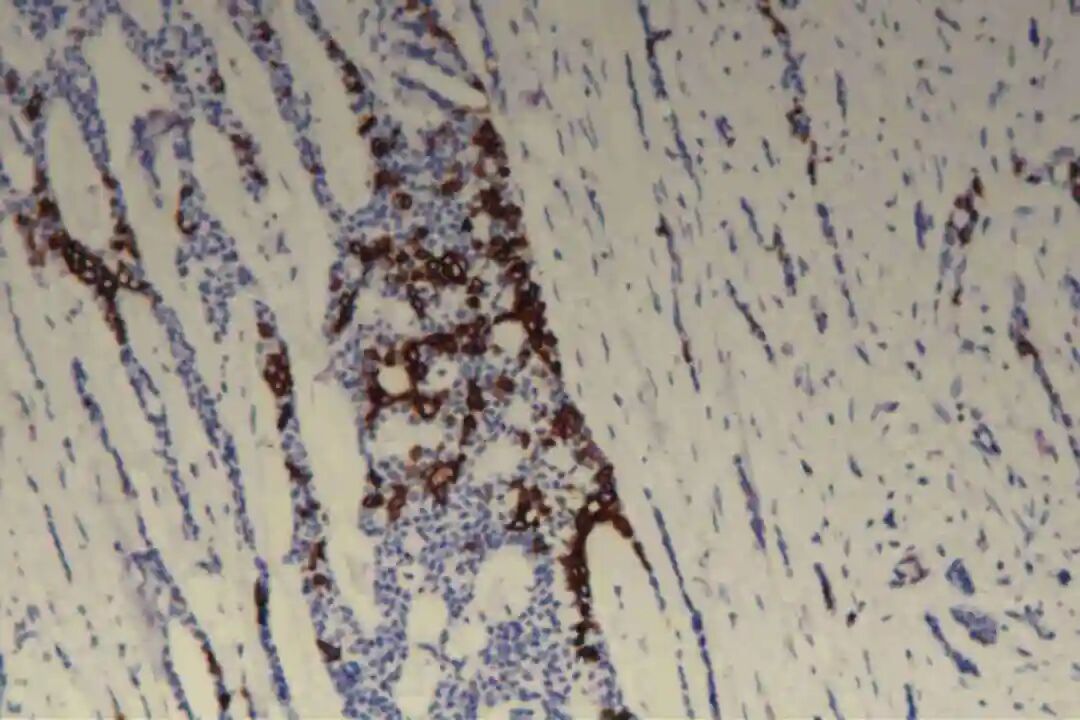

肌上皮细胞是PACC的重要组成部分,其标志物表达是诊断PACC的关键,主要表达p63、P40、平滑肌肌动蛋白(SMA)、肌动蛋白(Actin)及S-100蛋白,其中p63、P40呈弥漫阳性表达,SMA、S-100蛋白呈局灶或弥漫阳性表达。

此外,肿瘤细胞不表达神经内分泌标志物(CgA、Syn、CD56),可排除神经内分泌肿瘤;不表达GCDFP-15,可排除大汗腺来源肿瘤;基底膜物质(Ⅳ型胶原、laminin)阳性,主要分布于筛状结构、管状结构的腔隙周围及实性巢团的微小腔隙内,进一步支持PACC的诊断。